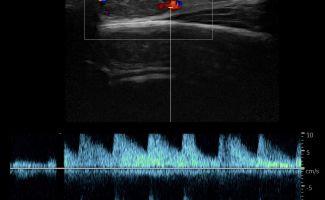

Η τεχνική του Έγχρωμου Doppler μελετάει την αγγείωση της βλάβης. Η τεχνική του Παλμικού Doppler μελετάει την παρουσία αρτηριακών ή φλεβικών στοιχείων εντός της βλάβης. Επίσης πολύ χρήσιμη είναι η Ελαστογραφική Μελέτη η οποία μελετάει τη σκληρότητας της βλάβης. Οι τεχνικές αυτές μας βοηθούν να χαρακτηρίσουμε αν η βλάβη είναι αγγειακού τύπου και αν έχει καλοήθη η ύποπτα χαρακτηριστικά.